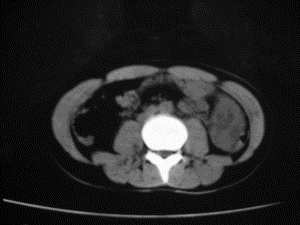

患者女,20岁,被车撞伤3小时,pe:全腹肌紧张,压痛反跳痛,以右上腹为著,肠鸣音减弱。有手术结果。![]() ![]() ![]() ![]() ![]() ![]() ![]() ![]() ![]() ![]() ![]() ![]() ![]() ![]() ![]() ![]() ![]() ![]() ![]() ![]() ![]() jiajie发言: ![]() 考虑空腔脏器穿孔。 dyqct发言:考虑:1、肝左叶外侧段断裂伤伴少量腹血。2、空腔脏器穿孔。 fangzheng发言:仅见腹腔内游离气体,提示空腔脏器穿孔。 guoke发言:胃内密度增高,肠腔内充满气体,考虑肠腔破裂出血 mmg94发言:胃后壁见一增厚软组织密度影,肝左叶前见游离气体影,左腹腔内局部肠管壁、系膜增厚。并见类圆形软组织。以上征象提示消化道管腔破裂,小肠、肠系膜挫裂伤,腹腔血肿形成。 拾荒者发言:肝实质密度不均匀,胃内见不均匀高密度影。考虑:肝挫裂伤,胃内应激性溃疡出血。 守望可可西里发言: 以下是引用jiajie在2006-6-20 15:49:00的发言:[br] [br][br]考虑空腔脏器穿孔。jiajie老师,我鼓起了很大的勇气才决定给您唱个反调儿,如果我错了,请您一定给我指出来,谢谢您了。我反复看了解剖图谱,觉得您所说的“考虑空腔脏器穿孔”上图所用箭头标明的不是游离气体。请您看以下几幅图片: ![]() ![]() ![]() ![]() ![]() ![]() ![]() ![]() 再请您看向医生老师发表的解剖图谱3幅 ![]() ![]() ![]() 这以下几幅图,我认为是肝包膜下积血。不过,说实在话,我没有发现有明显的肝挫裂伤。不对的地方请您一定指出来,再次感谢您了,jiajie 老师! ![]() ![]() ![]() ![]() 这下面几幅图片,我认为有明显的左中上腹部小肠损伤。 ![]() ![]() ![]() ![]() ![]() ![]() ![]() ![]() jiajie 老师,估计我说的是错误的,但我实在闹不明白,请您一定不要笑话我,并指出我的错误,以便于我减少工作中的失误。再次感谢您了,jiajie 老师! 至于胃内的不均匀高密度,我认为拾荒者战友说的有道理,胃内应激性溃疡出血和胃内容物混合所致。 手术结果:左肝叶(iv段)前缘长约8cm挫裂伤口,舌叶根部下< |